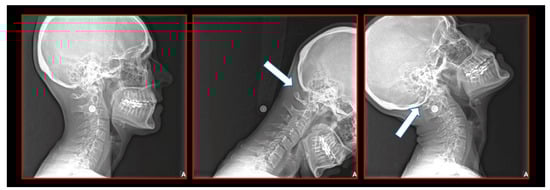

10.1. Neck X-ray

11.5. Axis and Atlas Derotation